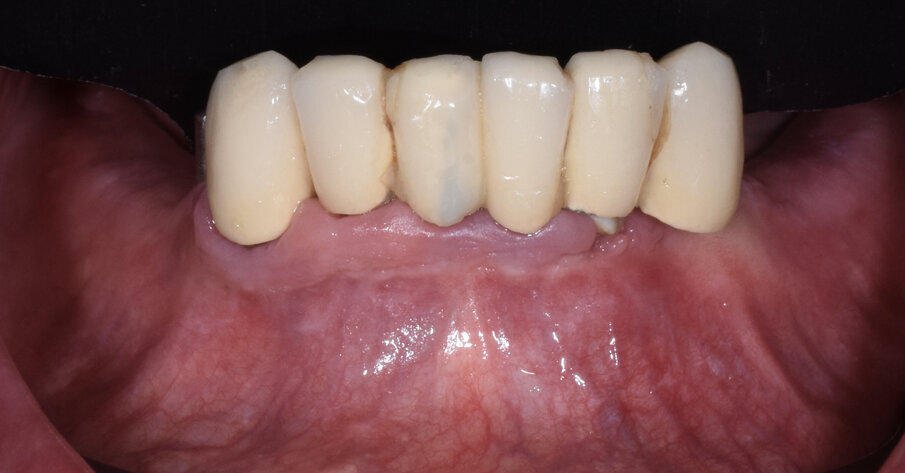

Fig. 21 - Carico immediato.

Fig. 22 - Visione occlusale carico immediato.